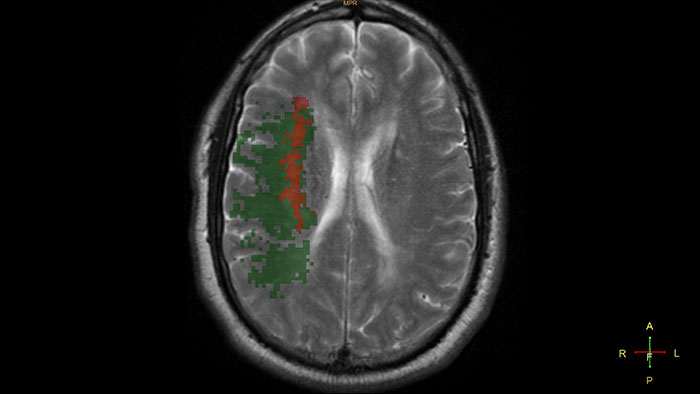

Determine areas of reduced cerebral blood flow as compared to the contralateral hemisphere

Generates qualitative and quantitative information about changes in image intensity over time. The application calculates and displays quantitative color maps of cerebral blood flow (CBF), cerebral blood volume (CBV), mean transit time (MTT) and time-to-peak (TTP), and provides summary maps which may help physicians in determining areas of reduced cerebral blood flow compared to the contra lateral hemisphere.

• Perfusion and summary maps can be generated automatically and sent to PACS for convenient reviewing.

• With studies of sufficient scan duration, permeability analysis can be used as an assessment of the contrast agent permeation of the blood-brain barrier.

• The default parameters and thresholds used to create the summary maps may be edited by the user according to the physician’s preference.

• Automatic motion correction that can be further refined manually if needed.

• Quality indicators (“traffic lights”) point at possible acquisition faults that may affect the results.

• Pre-defined ROI templates for systematic and reproducible quantitative regional results.